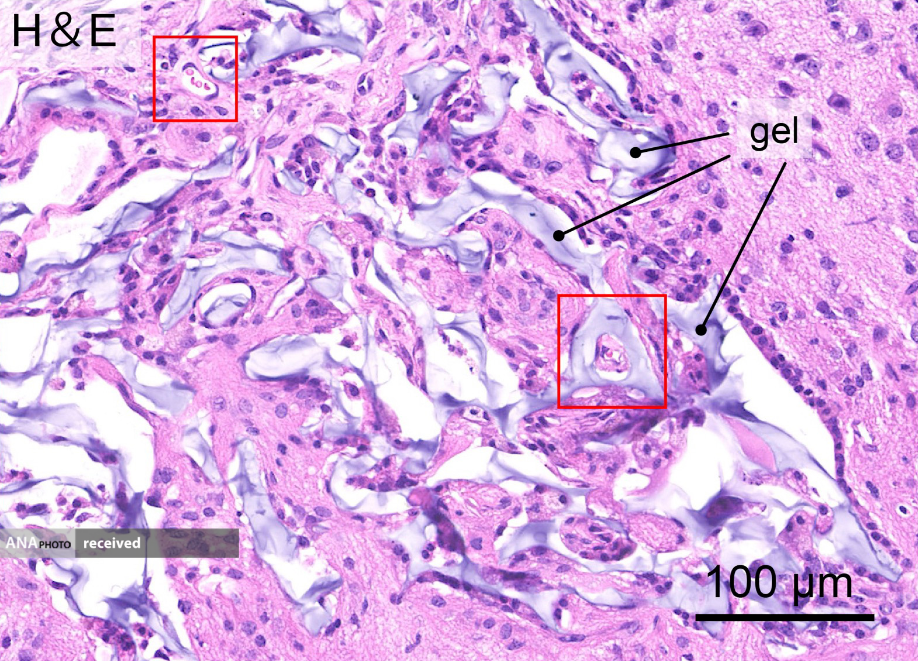

سلولهای بنیادی عصبی، ۶۴ روز پس از پیوند به هیدروژل (کادرهای قرمز رنگ عروق خونی را نشان میدهد)